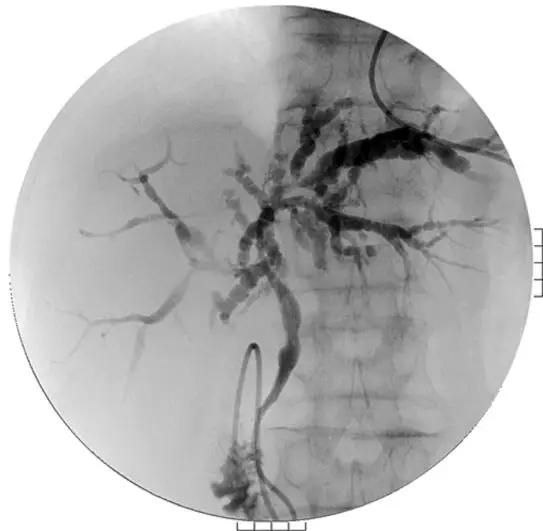

A.胆道影像学检查

ERCP:胆管狭窄与扩张交互,呈串珠状改变

多发短小狭窄,胆管环状受累

PTCD:胆管呈边缘不整羽毛状

ERC:胆管壁呈憩室样突出